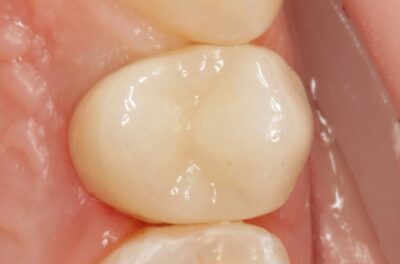

Специализация: терапия(эндодонтия), ортопедия, имплантология.